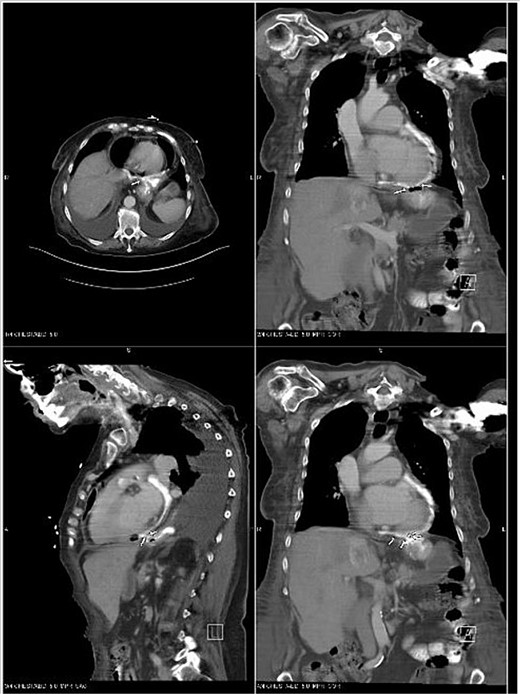

An echocardiogram revealed an EF of 45%–50%. The IVC was dilated and collapsed less than 50% with a sniff, suggesting high right atrial pressure. There was concern that a gastro-pericardial fistula caused the pneumopericardium, so another CT chest with oral contrast was ordered. The CT demonstrated the passage of the oral contrast into the pericardial space, confirming the gastro-pericardial fistula (Fig. 2).

CT Chest with oral contrast demonstrating gastropericardial fistula.